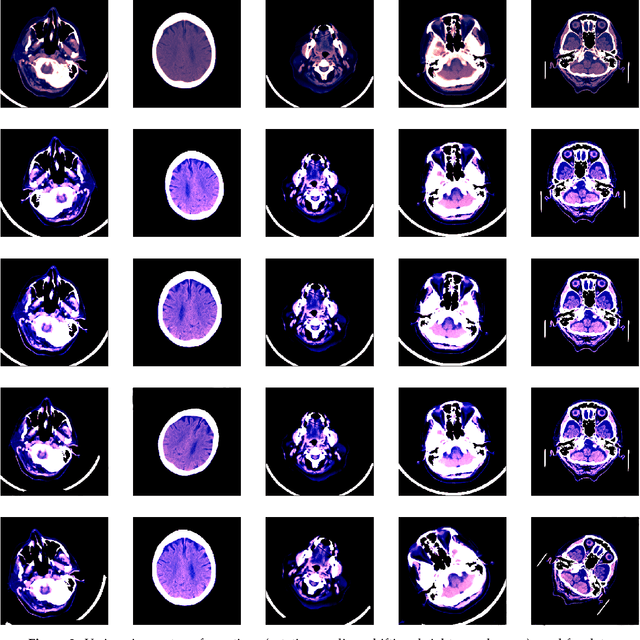

Abstract:In this paper, we present our system for the RSNA Intracranial Hemorrhage Detection challenge. The proposed system is based on a lightweight deep neural network architecture composed of a convolutional neural network (CNN) that takes as input individual CT slices, and a Long Short-Term Memory (LSTM) network that takes as input feature embeddings provided by the CNN. For efficient processing, we consider various feature selection methods to produce a subset of useful CNN features for the LSTM. Furthermore, we reduce the CT slices by a factor of 2x, allowing ourselves to train the model faster. Even if our model is designed to balance speed and accuracy, we report a weighted mean log loss of 0.04989 on the final test set, which places us in the top 30 ranking (2%) from a total of 1345 participants. Although our computing infrastructure does not allow it, processing CT slices at their original scale is likely to improve performance. In order to enable others to reproduce our results, we provide our code as open source at https://github.com/warchildmd/ihd. After the challenge, we conducted a subjective intracranial hemorrhage detection assessment by radiologists, indicating that the performance of our deep model is on par with that of doctors specialized in reading CT scans. Another contribution of our work is to integrate Grad-CAM visualizations in our system, providing useful explanations for its predictions. We therefore consider our system as a viable option when a fast diagnosis or a second opinion on intracranial hemorrhage detection are needed.